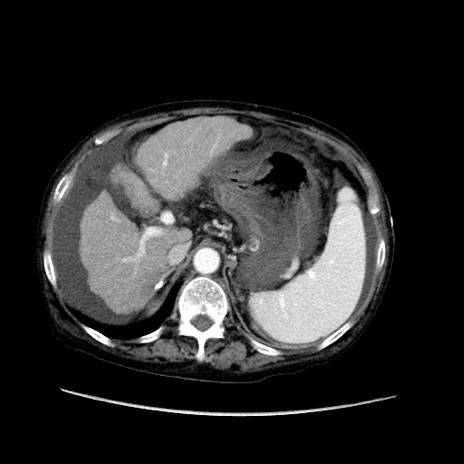

症例31(横断像)

【症例】80歳代 女性

【主訴】腹部膨満感

【現病歴】他院にて肝硬変にてフォロー中。1週間前から便秘、腹部膨満感、臍部腫瘤あり受診となる。

【既往歴】肝硬変

【身体所見】腹部膨隆あり、皮膚変化なし、疼痛なし。

【データ】WBC 4600、CRP 0.25